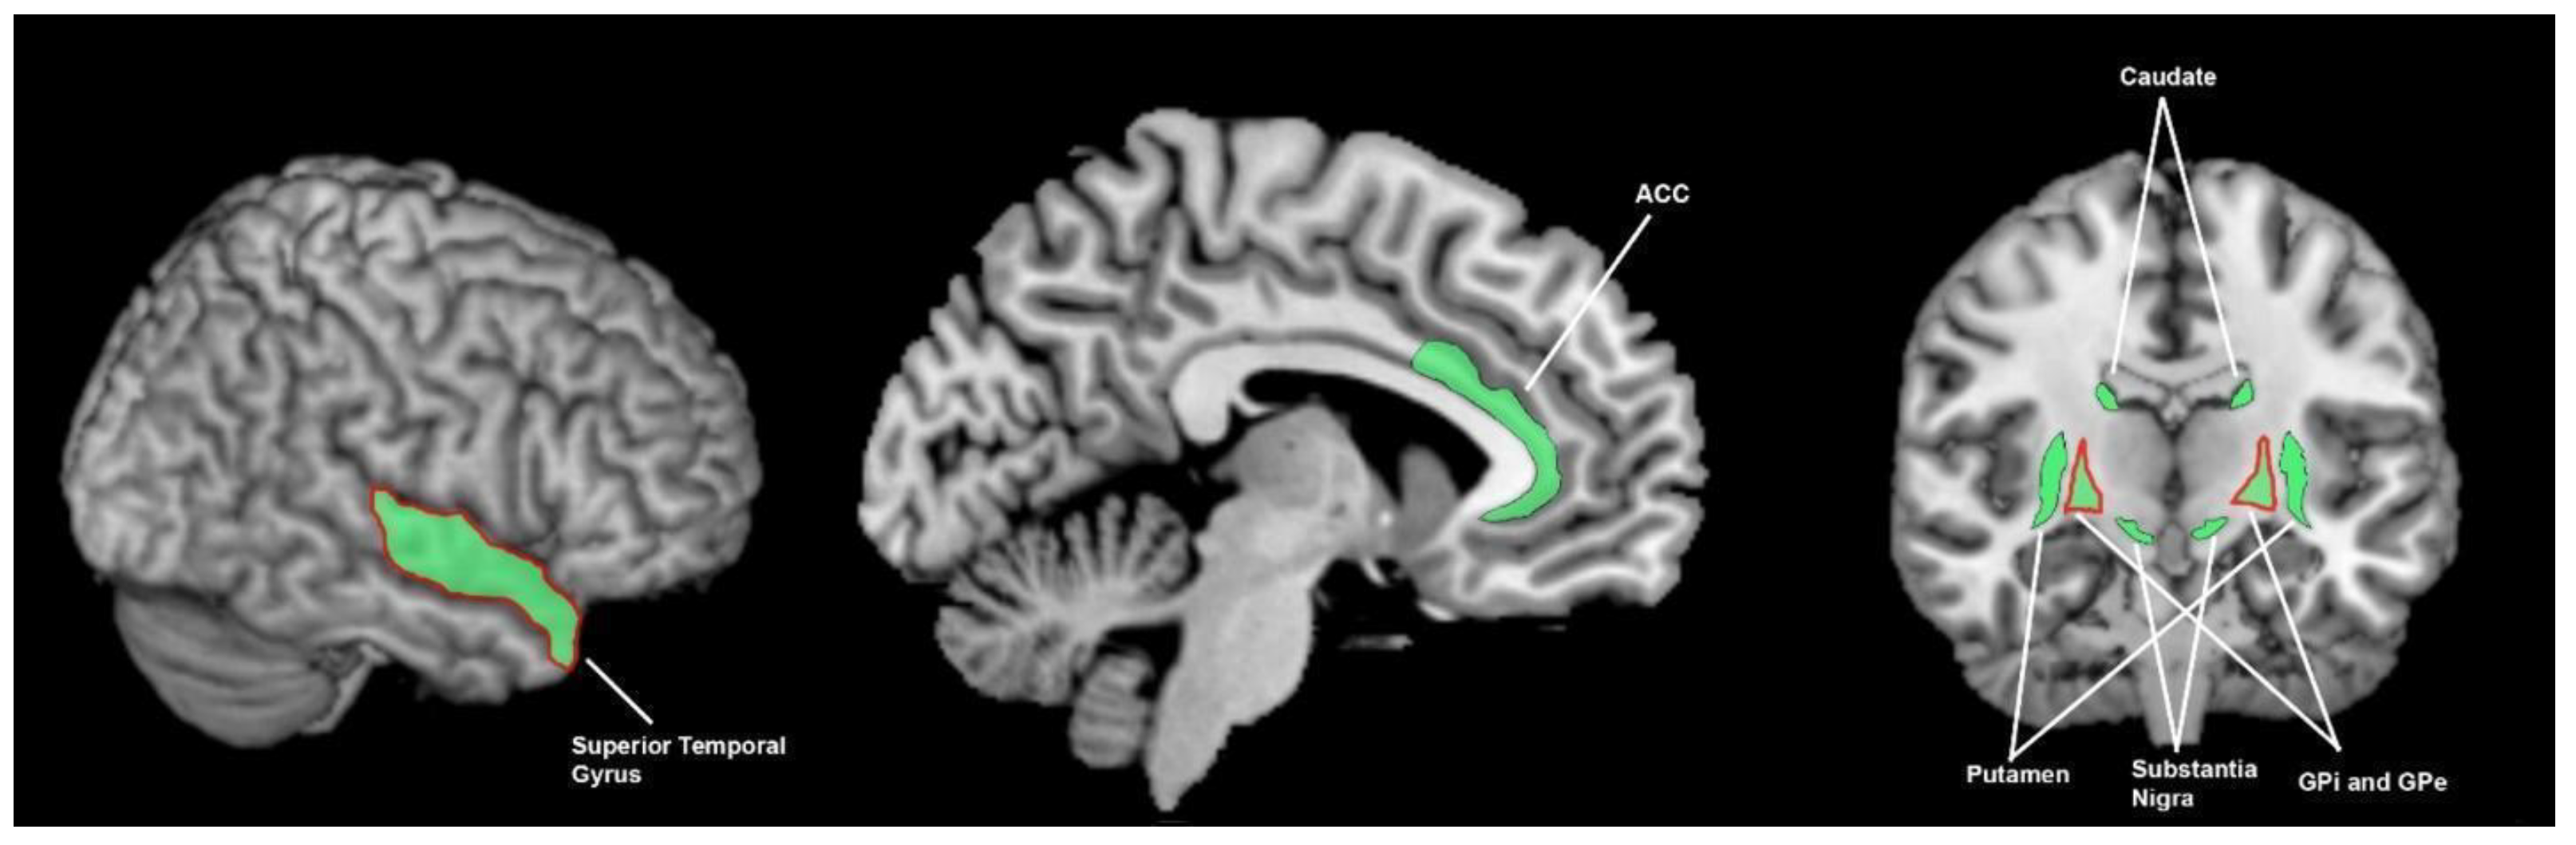

3.3.3. What Brain Areas Are Involved in Auditory Processing in Healthy Cohorts?

3.3.4. What Brain Areas Are Found to Function Abnormally during Auditory Processing in Patients with Parkinson’s Disease?

3.3.5. What Brain Areas Are Involved in Visual Processing in Healthy Cohorts?

3.3.6. What Brain Areas Are Found to Function Abnormally during Visual Processing in People with Parkinson’s Disease?

3.4. The Breadth of Sensory Response and Multisensory Response of the Basal Ganglia

4.1. What Brain Areas Are Involved in Sensory Processing, What Are the Abnormalities in Parkinson’s Disease, and What Is the Importance of the Basal Ganglia?